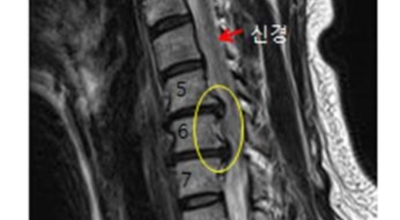

경추 사이의 추간판(디스크)이 탈출 또는 파열되어 경추신경이 자극이나 압박을 받아 통증이 생기는 증상을 말해요. 경추는 운동성이 큰 부위로 추간판이 압력을 받으면 튀어나와 척수나 신경을 압박하게 되는데요 목디스크는 퇴행성 변화 이후에 발생되기 때문에 많은 환자들이 만성적인 통증을 지니고 있는 경우가 많아요. 급성으로 생기는 경우는 교통사고, 추락, 스포츠 활동에 의한 목 부상으로 나타나기도 해요. 20대부터 가벼운 초기 증상으로 시작하여 옳지 않은 습관으로 악화되거나 호전되기를 반복해요. 나이가 들면 퇴행성 변화로 40~50대에 가장 많은 환자 수를 보인다고 합니다

목디스크는 본래의 자리에서 튀어나온 디스크의 일부 및 척추 뼈에서 생긴 골극이 양쪽 어깨, 팔, 손으로 가는 신경을 눌러 발생되는 질병입니다. 따라서 신경이 목 부위에서 훼손을 입으면 팔과 손으로 통증이 뻗어나가는 방사통이 생겨나게 되어요.

비수술적 치료가 효과가 없다거나 디스크의 신경압박이 정도가 심한 경우엔 시술할 관조차 들어갈 공간이 없으니 비수술을 고집하는 경우 주변의 정상조직까지 훼손이 될 위험이 있답니다. 미세 현미경 수술이나 인공 디스크 치환술 및 경추유합술을 통해서 치료가 가능한데 가급적 비수술치료가 권장되지만 정확한 진단이 먼저되어야 하기 때문에 자세한 사항은 전문의와 상담해서 결정하는 것이 좋을겁니다.